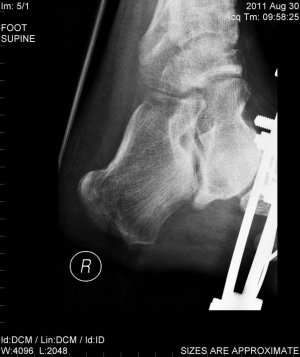

Возник вопрос об упражнениях для реабилитации после перелома голени и пятки (реабилитолог поликлиники сейчас в отпуске). Перелом произошел 3 месяца назад, наложение аппарата Илизарова осуществлено на неделю позже.

На данный момент могу поднимать стопу на 1 см максимум со слабым усилием, также создавать небольшое на опускание стопы. Пальцы но могу опускать (вжимать) нормально, но принципиально не могу поднимать (разжимать). Опухлость верхней части стопы держится все 3 месяца.